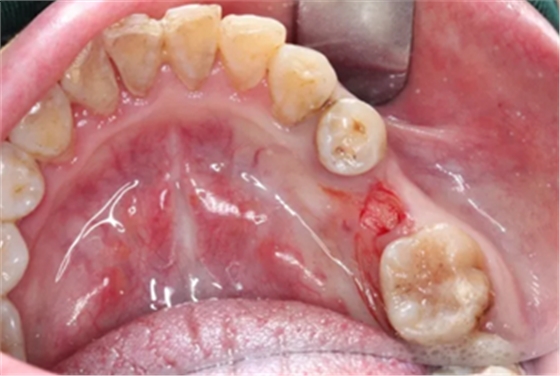

为缩短种植治疗的时间,保护患者软组织形态、维持牙槽骨高度和骨量,使用Implant Guide™全程导板、Alpha-Bio Tec ICE种植系统,施行数字化全程导航以及椅旁即刻修复种植术,数字化微创种植手术便捷顺利,仅用17分钟完成全程种植手术。

术前术后CBCT数据对比分析,植体就位准确。